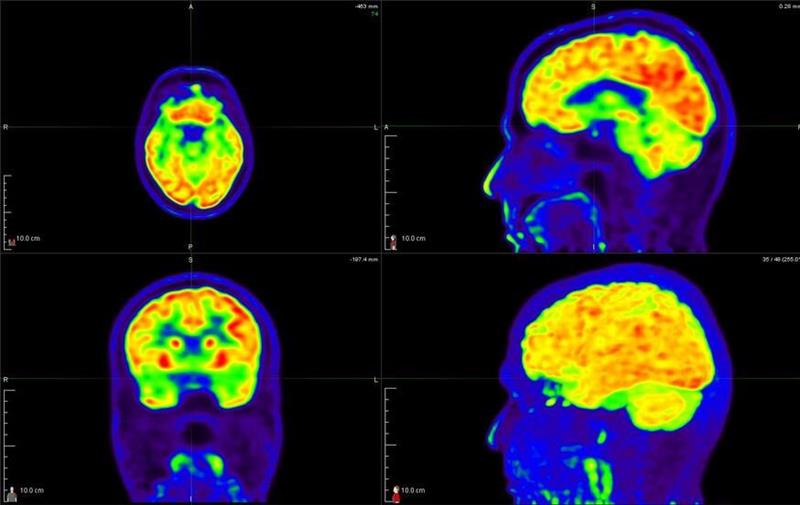

India’s hybrid imaging landscape is entering a pivotal expansion phase as the incidence of cancer and cardiac diseases rises beyond major metropolitan areas. National programs under Ayushman Bharat as well as Pradhan Mantri–Ayushman Bharat Health Infrastructure Mission (PM-ABHIM), and the expansion of state cancer institutes are pushing hospitals toward more reliable functional imaging. addresses this need by offering a cost-effective alternative in areas with limited PET access. This makes it particularly valuable in secondary cities preparing for larger oncology and cardiology caseloads.